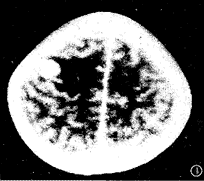

图3 右额顶叶多环形强化病灶,病灶周围明显水肿。